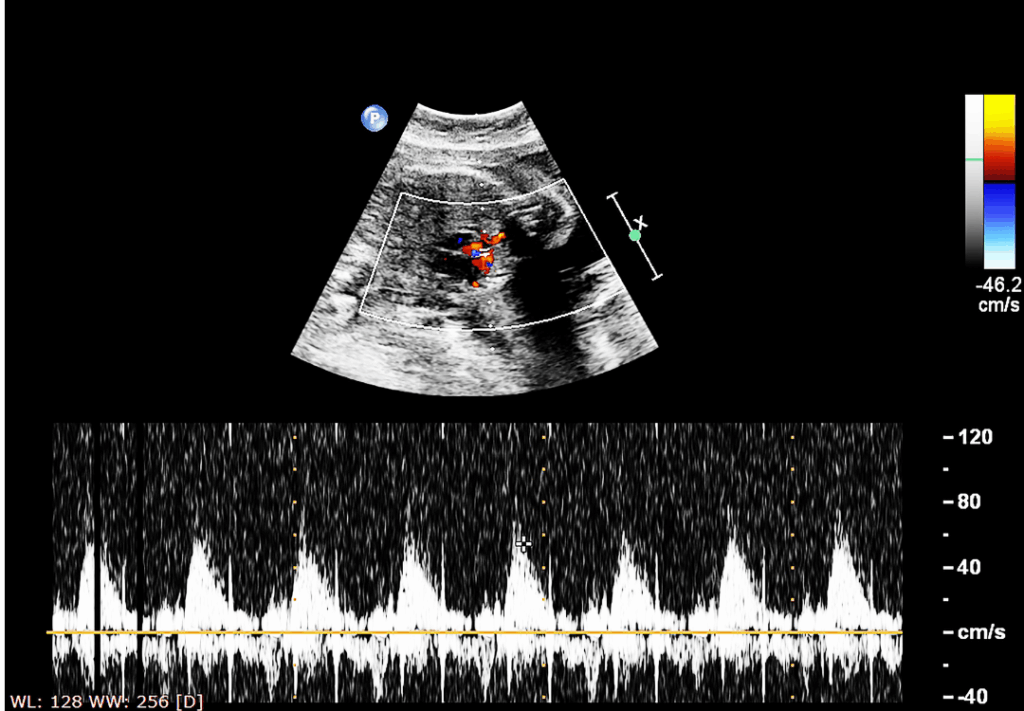

A detailed fetal heart scan is recommended between 18–24 weeks to evaluate congenital heart defects (CHDs). Our specialist fetal echocardiography services in Miraj help:

Assess heart structure and function

Detect rhythm abnormalities and defects

Plan for early interventions if needed